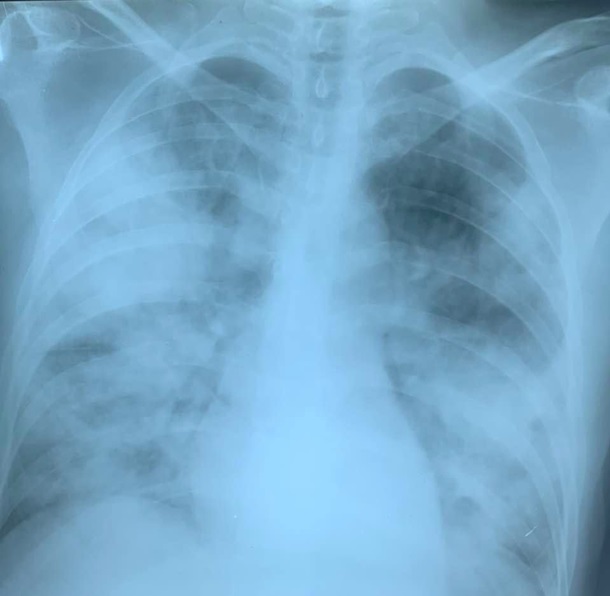

На фото: такие необратимые изменения в легких наступают в сроки от 3 до 5-7 дней. Берегите себя.